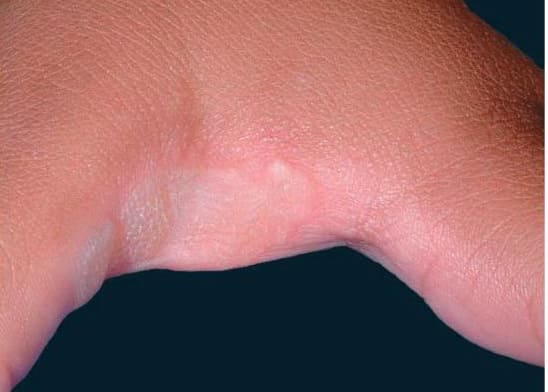

Classic porokeratosis of Mibelli begins during infancy or childhood as asymptomatic small brown to skin-colored annular papules with a characteristic annular border . The well-demarcated hyperkeratotic border is usually more than 1 mm in height, with a characteristic longitudinal furrow. The center of the lesion may be hyperpigmented, hypopigmented, depressed, atrophic, or anhidrotic. Lesions range in diameter from millimeters to several centimeters, but giant lesions measuring up to 20 cm may occur. Such giant porokeratoses are rare and occur predominantly on the lower leg and foot. Large lesions are associated with a higher malignant potential. Multiple lesions may arise; however, they are usually regionally localized and unilateral. The condition may be familial and inherited as an autosomal dominant trait. Lesions persist indefinitely.